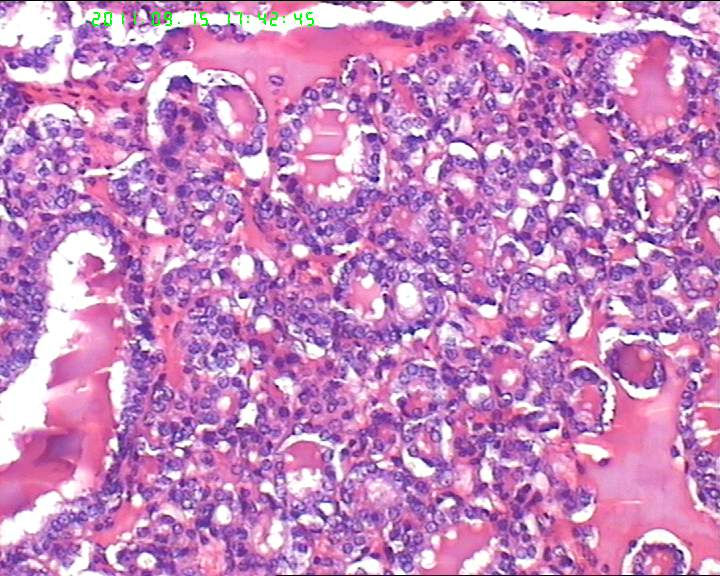

甲状腺右下极一肿物,3*3大小,切面灰红实性质韧,可见部分包膜,一侧可见一空腔,未见内容物。